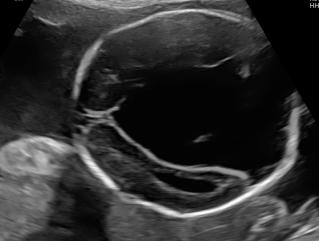

28-jährige Primigravida mit spontan entstandener dichorialer Zwillingsschwangerschaft. Unauffälliger Fetus 1, Fetus 2 zeigt zerebrale Auffälligkeiten (Bild, 26 1/7 Wochen).

Wo sind die Seitenventrikel?

Was könnte die Ursache sein für diese Anomalie?